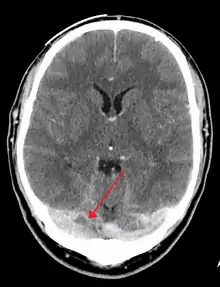

There are various neuroimaging investigations that may detect cerebral sinus thrombosis. Cerebral edema and venous infarction may be apparent on any modality, but for the detection of the thrombus itself, the most commonly used tests are computed tomography (CT) and magnetic resonance imaging (MRI), both using various types of radiocontrast to perform a venogram and visualise the veins around the brain.[2]

Computed tomography, with radiocontrast in the venous phase (CT venography or CTV), has a detection rate that in some regards exceeds that of MRI. The test involves injection into a vein (usually in the arm) of a radioopaque substance, and time is allowed for the bloodstream to carry it to the cerebral veins – at which point the scan is performed. It has a sensitivity of 75–100% (it detects 75–100% of all clots present), and a specificity of 81–100% (it would be incorrectly positive in 0–19%). In the first two weeks, the "empty delta sign" may be observed (in later stages, this sign may disappear).[8] The empty delta sign is characterized by enhancement of the dural wall without intra-sinus enhancement.[4]